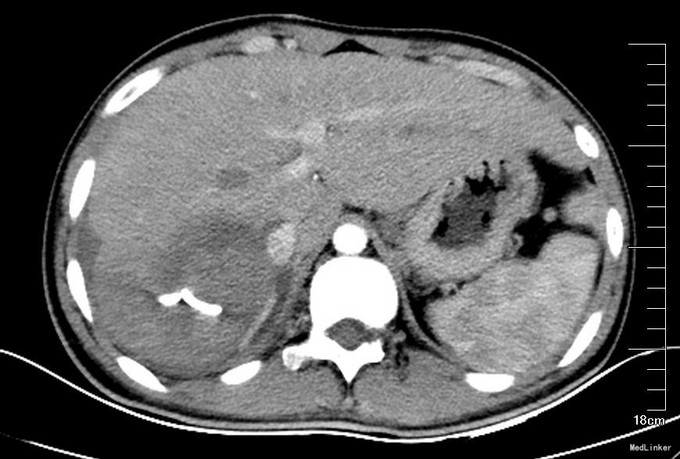

患者术前CT因为外院检查,未得以资料。介入术后17天复查CT(图1):可见引流管留置,肝右后叶占位,6*4cm,实性为主。术后2个月行肝脏增强CT复查(图2):肝右后叶病变,液性区域不多。术后5个月再次行MRI(图3):肝右后叶占位,实性部分占大部分,且与其他肝脏各段似有分界。考虑穿刺引流不能达到消除病灶。行外科手术治疗。手术方案为:肝部分切除,完整切除占位(图4)送冰冻病理回报:炎性假瘤,伴肉芽肿病变。术后患者恢复良好,出院。石蜡病理:考虑结核。